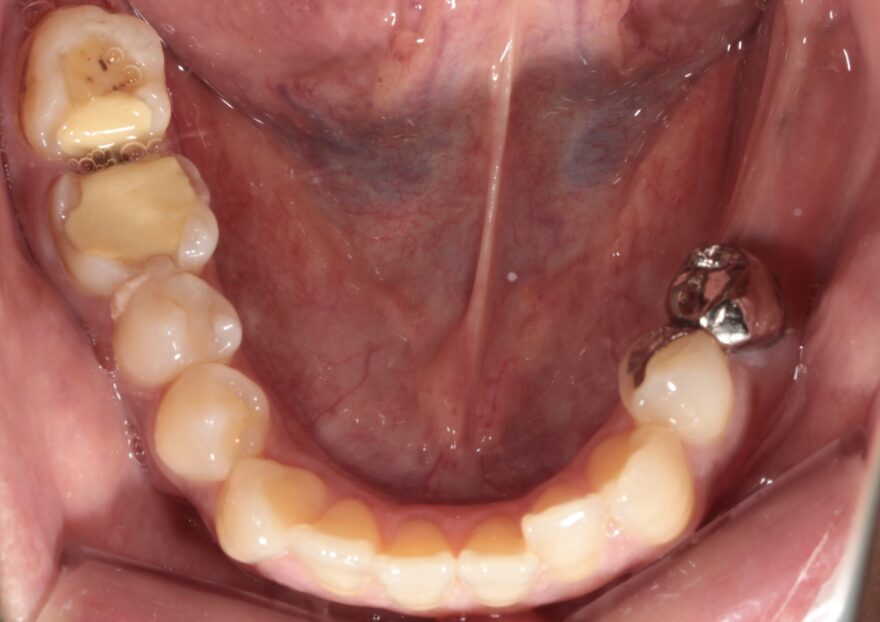

初診時の口腔内写真

左下の奥歯が崩壊しています。

右下の奥歯を失い、噛み合わせが歪んでいることが分かります。

右上の八重歯が気になります。